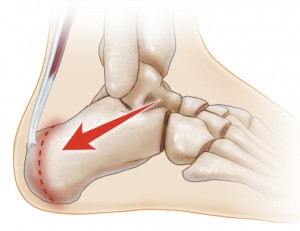

تاندون یا زردپی آشیل که قویترین تاندون بدن است به آپوفیز استخوان پاشنه (کالکانه) میچسبد و کشش تاندون موجب میشود صفحه رشد بین آپوفیز و تنه استخوان پاشنه تحت فشار قرار گرفته و علائم بیماری بروز کند. آپوفیز قسمتی از استخوان است که با تنه اصلی استخوان به توسط صفحه رشد جدا شده است . کشش تاندون آشیل بر اثر انجام ورزش هایی مانند دویدن و پریدن بخصوص بر روی زمین های سفت بیشتر میشود. ورزش های بسکتبال، فوتبال و ژیمناستیک این تاندون را بشدت تحت کشش قرار میدهد. ایستادن به مدت طولانی و استفاده از کفش نامناسب هم میتواند موجب کشیده شدن بیش از حد تاندون آشیل شود .

بیماری سیور Sever’s disease که به آن آپوفیزیت کالکانه Calcaneal apophysitis هم میگویند نوعی التهاب در صفحه رشد استخوان پاشنه است که موجب درد در آن ناحیه میشود . بیماری سیور یکی از علل شایع درد پاشنه در نوجوانان در حال رشد بخصوص بچه های با فعالیت های بدنی زیاد است. این بیماری بیشتر در دوره رشد سریع نوجوانان ایجاد میشود. بیماری سیور از این نظر تا حدی شبیه بیماری ازگود اشلاتر در ناحیه زانو است .

بنظر میرسد در دوران رشد سریع نوجوانان سرعت رشد استخوان ها بیش از عضلات و تاندون ها است. در ناحیه ساق این وضعیت منجر به کوتاه ماندن نسبی عضلات پشت ساق نسبت به استخوان درشت نی شده و در نتیجه عضلات پشت ساق و بدنبال آن تاندون آشیل تحت کشش قرار میگیرد .